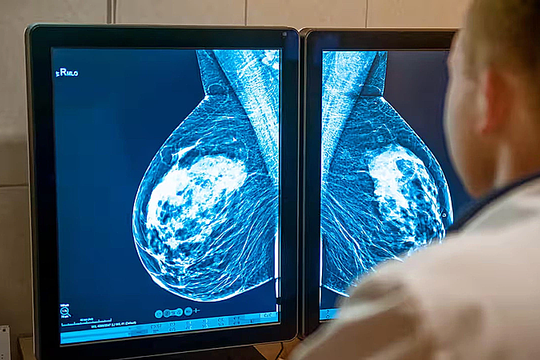

Khi nào nên chụp X-quang tầm soát ung thư vú?

23/11/2025 08:00

Tôi 25 tuổi, đã kết hôn và sinh con, thỉnh thoảng thấy đau tức, ngứa, tiết dịch nhũ hoa. Đây có phải dấu hiệu ung thư vú, chụp X-quang tầm soát có gây hại không? (Lan, Hà Nội)

Nhiều phụ nữ phát hiện ung thư vú nhờ tầm soát sớm

02/11/2025 11:20

Việc tầm soát sớm giúp phát hiện các khối u chỉ 1-2 cm, ngay cả khi chưa thể sờ thấy, mang lại hiệu quả điều trị cao và cơ hội chữa khỏi hoàn toàn cho nhiều phụ nữ.